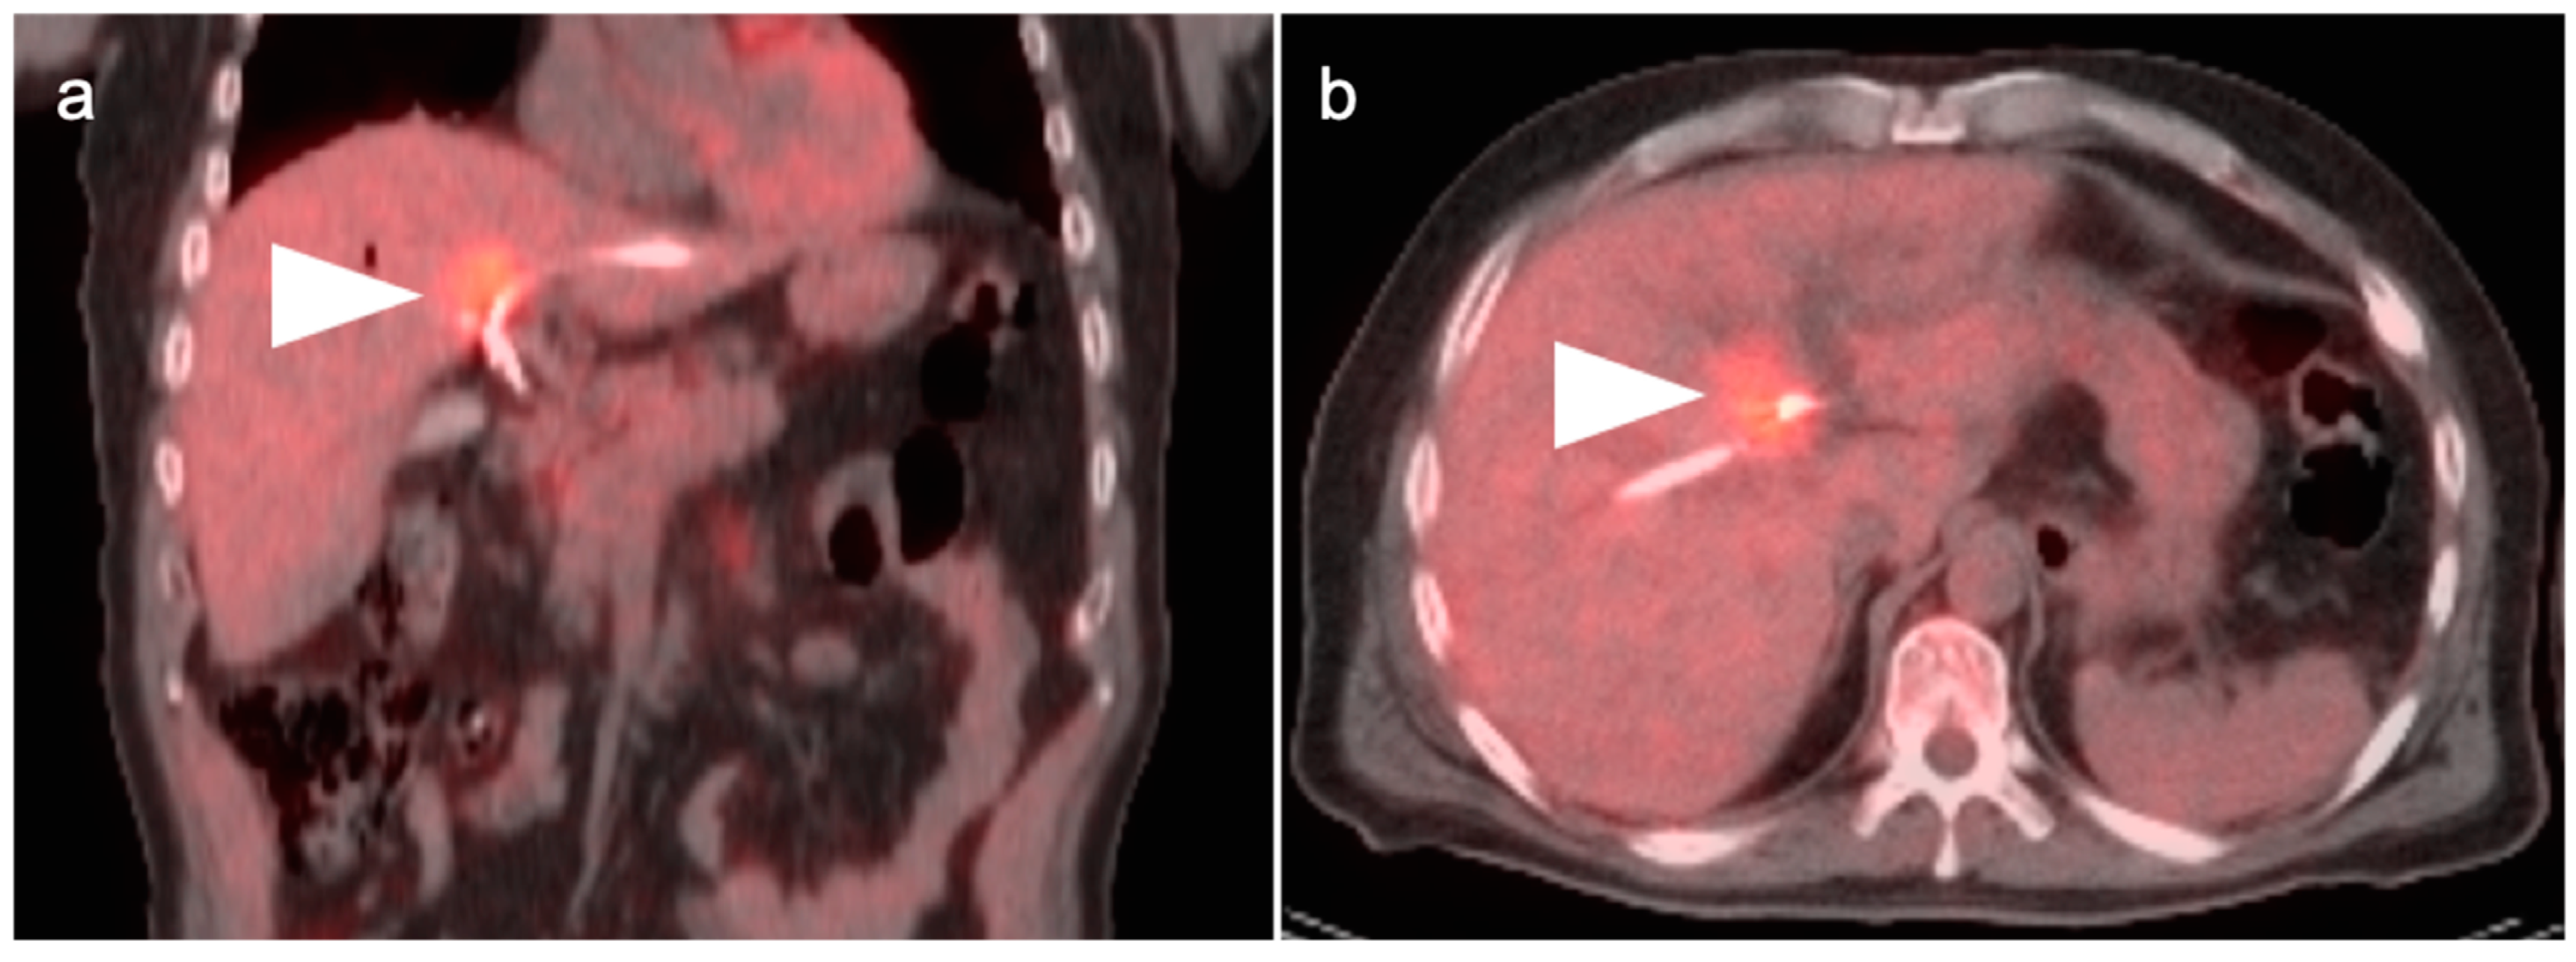

4. Hepatocellular Carcinoma

- Talbot, J.N.; Fartoux, L.; Balogova, S.; Nataf, V.; Kerrou, K.; Gutman, F.; Huchet, V.; Ancel, D.; Grange, J.D.; Rosmorduc, O. De-tection of hepatocellular carcinoma with PET/CT: A prospective comparison of 18F-fluorocholine and 18F-FDG in patients with cirrhosis or chronic liver disease. J. Nucl. Med. 2010, 51, 1699–1706. [Google Scholar] [CrossRef] [PubMed]

- Yamamoto, Y.; Nishiyama, Y.; Kameyama, R.; Okano, K.; Kashiwagi, H.; Deguchi, A.; Kaji, M.; Ohkawa, M. Detection of Hepatocellular Carcinoma Using 11C-Choline PET: Comparison with 18F-FDG PET. J. Nucl. Med. 2008, 49, 1245–1248. [Google Scholar] [CrossRef] [PubMed]

- Kesler, M.; Levine, C.; Hershkovitz, D.; Mishani, E.; Menachem, Y.; Lerman, H.; Zohar, Y.; Shibolet, O.; Even-Sapir, E. 68Ga-PSMA is a novel PET-CT tracer for imaging of hepatocellular carcinoma: A prospective pilot study. J. Nucl. Med. 2019, 60, 185–191. [Google Scholar] [CrossRef] [PubMed]

- Thompson, S.M.; Suman, G.; Torbenson, M.S.; Chen, Z.E.; Jondal, D.E.; Patra, A.; Ehman, E.C.; Andrews, J.C.; Fleming, C.J.; Welch, B.T.; et al. PSMA as a Theranostic Target in Hepato-cellular Carcinoma: Immunohistochemistry and 68 Ga-PSMA-11 PET Using Cyclotron-Produced 68 Ga. Hepatol Commun. 2021, 6, 1172–1185. [Google Scholar] [CrossRef]

- Gündoğan, C.; Ergül, N.; Çakır, M.S.; Kılıçkesmez, Ö.; Gürsu, R.U.; Aksoy, T.; Çermik, T.F. 68Ga-PSMA PET/CT Versus 18F-FDG PET/CT for Imaging of Hepatocellular Carcinoma. Mol. Imaging Radionucl. Ther. 2021, 30, 79–85. [Google Scholar] [CrossRef]

- Hirmas, N.; Leyh, C.; Sraieb, M.; Barbato, F.; Schaarschmidt, B.M.; Umutlu, L.; Nader, M.; Wedemeyer, H.; Ferdinandus, J.; Rischpler, C.; et al. 68Ga-PSMA-11 PET/CT Improves Tumor Detection and Impacts Management in Patients with Hepatocellular Carcinoma. J. Nucl. Med. 2021, 62, 1235–1241. [Google Scholar] [CrossRef]